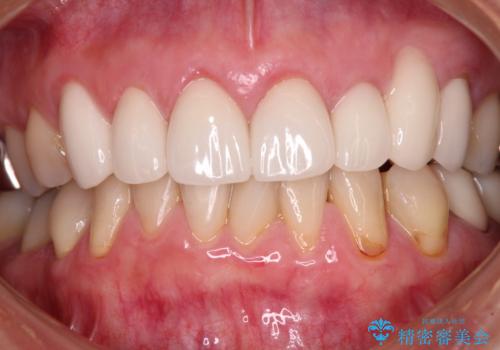

歯肉移植による根面被覆の結果、しみる症状は一切なくなりました。

歯肉の厚みが増したため、歯肉退縮のリスクが軽減されましたが、定期的に症状が再発していない確認していくことになります。